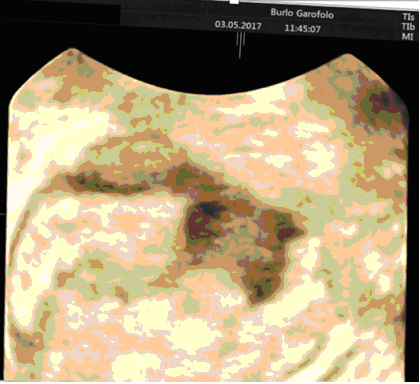

Fig. n. 2 Immagine di nodulo endometriosico intestinale in ecografia 3D

Fig.n.3  Immagine di nodulo endometriosico intestinale nella rettosonografia

L'aggiunta della tecnologia tridimensionale (3D) è relativamente nuova ed alcuni studi hanno dimostrato che questo approccio potrebbe garantire prestazioni migliori rispetto alle immagini bidimensionali classiche, con il vantaggio inoltre di esplorare ed elaborare le immagini non in presenza della paziente, consentendo a più lettori di studiare i dati ecografici. Un ulteriore step aggiuntivo è rappresentato dall’ecografia modificata”. Si effettua a discrezione dell’ecografista per migliorare la definizione diagnostica su indicazione delle localizzazioni di patologia: esame ecografico guidato dal dolore; esame ecografico eseguito con rettosonografia o con la sonovaginografia e l’ecografia tridimensionale. L’ecografia modificata ha dimostrato una migliore definizione diagnostica rispetto alla metodica tradizionale nonostante la scarsità degli studi precluda una valutazione di tipo statistico.

Da un recente consenso internazionale l’ecografia transvaginale emerge come la tecnica di imaging di prima linea grazie alla sua disponibilità e al costo relativamente basso pur presentando solo nelle mani di operatori dedicati un'alta affidabilità diagnostica che tuttavia varia a seconda delle sedi studiate. A differenza di altre tecniche di imaging sfrutta lo studio della dinamicità degli organi che aiuta ad approfondire nello specifico proprio le sedi di maggiore dolorabilità. Tuttavia, soprattutto nello studio dell'endometriosi, la metodica è fortemente operatore-dipendente, la cosiddetta Ecografia Pelvica di II livello.

Un accurato studio delle localizzazioni endometriosiche è di importanza fondamentale per una corretta pianificazione terapeutica che sia medica e/o chirurgica al fine di evitare la progressione di malattia che in stadi avanzati può danneggiare in maniera irreversibile non solo gli organi dell’apparato riproduttivo femminile ma anche organi limitrofi ad esso (vescica ed ureteri, intestino, strutture muscolari e fasciali).